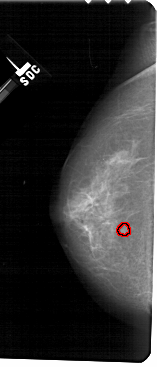

A_1373_1.LEFT_MLO

LEFT_MLO LINES 5446 PIXELS_PER_LINE 2581 BITS_PER_PIXEL 12 RESOLUTION 43.5 OVERLAY

FILE: A_1373_1.LEFT_MLO.OVERLAY

TOTAL_ABNORMALITIES 1

ABNORMALITY 1

LESION_TYPE MASS SHAPE OVAL MARGINS CIRCUMSCRIBED

ASSESSMENT 3

SUBTLETY 4

PATHOLOGY BENIGN

TOTAL_OUTLINES 1

BOUNDARY